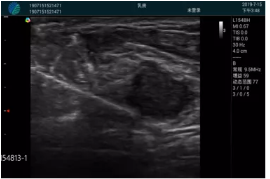

腺體內(nèi)部清晰顯示一低回聲塊影,形態(tài)不規(guī)則,邊界模糊,邊緣呈毛刺狀,內(nèi)部見砂礫樣鈣化

M20引導(dǎo)下穿刺活檢術(shù)

M20引導(dǎo)下平面內(nèi)穿刺取出的腫塊組織